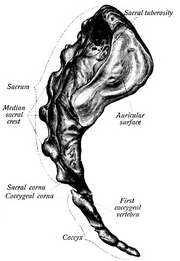

في البشر، العجز sacrum ( []ˈsækrəm[] أو []ˈseɪkrəm[]; مفرده: sacrums أو sacra)، هي عظام كبيرة، مثلثة الشكل، تقع على قاعدة العمود الفقري وعلى الجزء العلوي، الخلفي لتجويف الحوض، حيث تكون مغروزة مثل الوتد بين عظام الورك. الجزء العلوي منها تتصل بالفقرة القطنية، والجزء السفلي منها متصلة بالعصعص. عادة، يبدأ العجز كفقرة خامسة غير ملتحمة تبدأ بالالتحام في عمر 16-18 سنة وعادة ما يكتمل التحامها كعظمة واحدة في الرابعة والثلاثين.